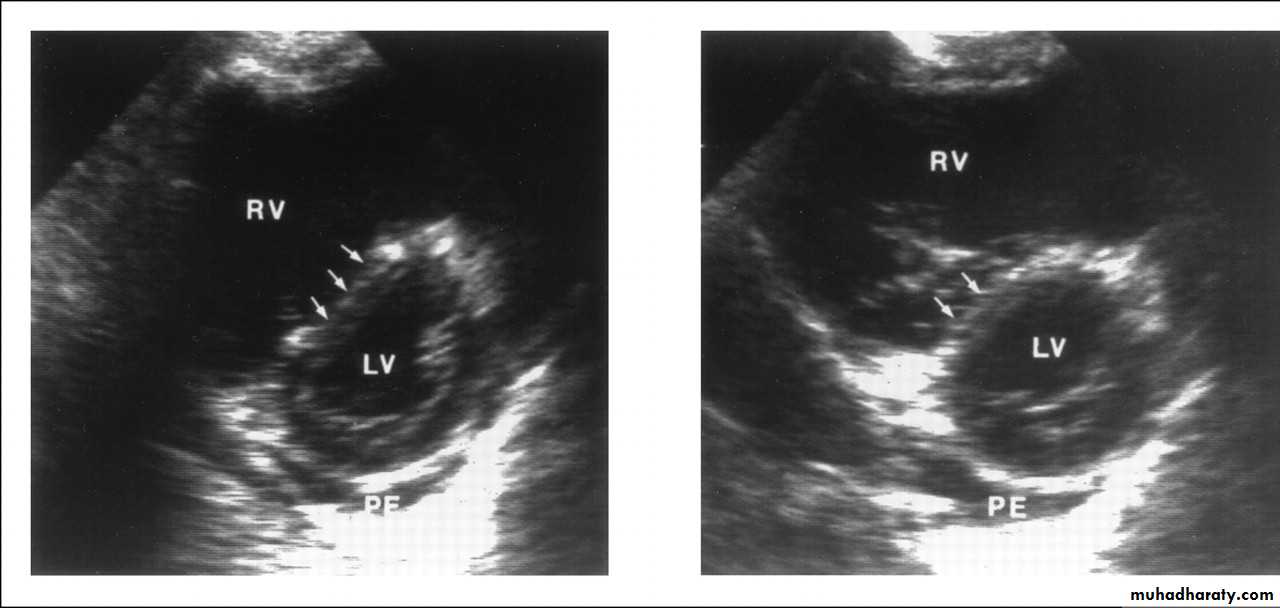

It is helpful in the evaluation of patients with acute circulatory collapse.

Acute right ventricular dilatation is usually present in massive PEA thrombus may be visible.

Alternative diagnosis, like heart failure and pericardial tamponade can be excluded

Echocardiography